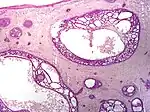

Nodular basal-cell carcinoma (also known as "classic basal-cell carcinoma") accounts for 50% of all BCC.[27] It most commonly occurs on the sun-exposed areas of the head and neck.[28]: 748 [29]: 646 Histopathology shows aggregates of basaloid cells with well-defined borders, showing a peripheral palisading of cells and one or more typical clefts.[27] Such clefts are caused by shrinkage of mucin during tissue fixation and staining.[30] Central necrosis with eosinophilic, granular features may be also present, as well as mucin. The heavy aggregates of mucin determine a cystic structure. Calcification may be also present, especially in long-standing lesions.[27] Mitotic activity is usually not so evident, but a high mitotic rate may be present in more aggressive lesions.[27] Adenoidal BCC can be classified as a variant of NBCC, characterized by basaloid cells with a reticulated configuration extending into the dermis.[27]

- Cleft.